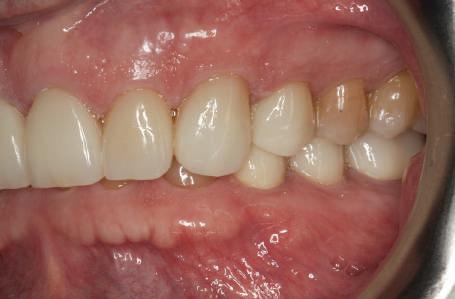

Cazul (2)

Repreparea intraorală a bonturilor cu amprente extraorale

Acest caz prezenta probleme de recesie similare cu cele menţionate anterior. Deşi bonturile au fost re-preparate intraoral pentru a urma noile margini tisulare, s-a decis amprentarea în afara cavităţii orale pentru a evita manipularea ţesutului pacientului cu biotip subţire. Fiecare bont individualizat s-a îndepărtat şi s-au inserat imediat bonturi de vindecare pentru a evita colapsul ţesuturilor.

Atitudine: Fiecare bont individualizat s-a aplicat pe câte un analog de implant. Fig. 6 prezintă bontul nou preparat pe analogul său cu inel de cupru de dimensiuni mari pentru a susţine

materialul de amprentare (alternativ, s-ar fi putut utiliza o lingură de amprentare universală pe cadran pentru a asigura suport pentru materialul de amprentare). Fig. 7 prezintă bontul individualizat cu ceară aplicată pentru a preveni pătrunderea materialului de amprentare în camera de acces a şurubului, iar fig. 8 ilustrează tehnica de amprentare care evită necesitatea plasării unui şnur de retracţie în şanţ în jurul implantului. Această tehnică este, de asemenea, utilă pentru adăugarea la marginile restaurării provizorii.

Cazul (2): Repreparea intraorală a bonturilor cu amprente extraorale

Figurile

6. Bontul nou preparat pe analog.

7. Bont individualizat cu vată şi ceară.

8. Tehnica de amprentare.